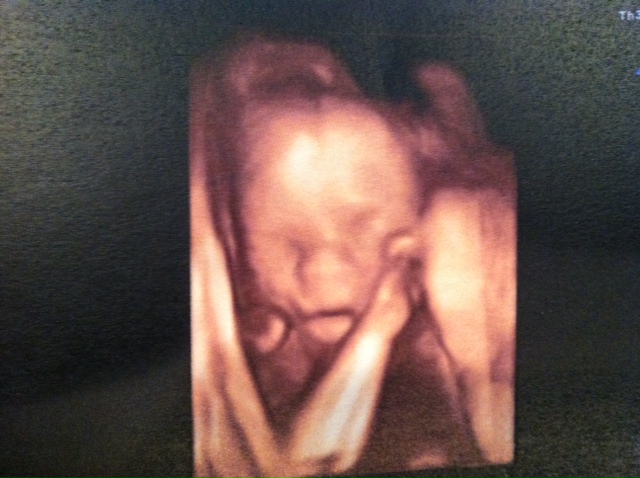

Here are a few of the recent pics (he was being a bit camera shy):